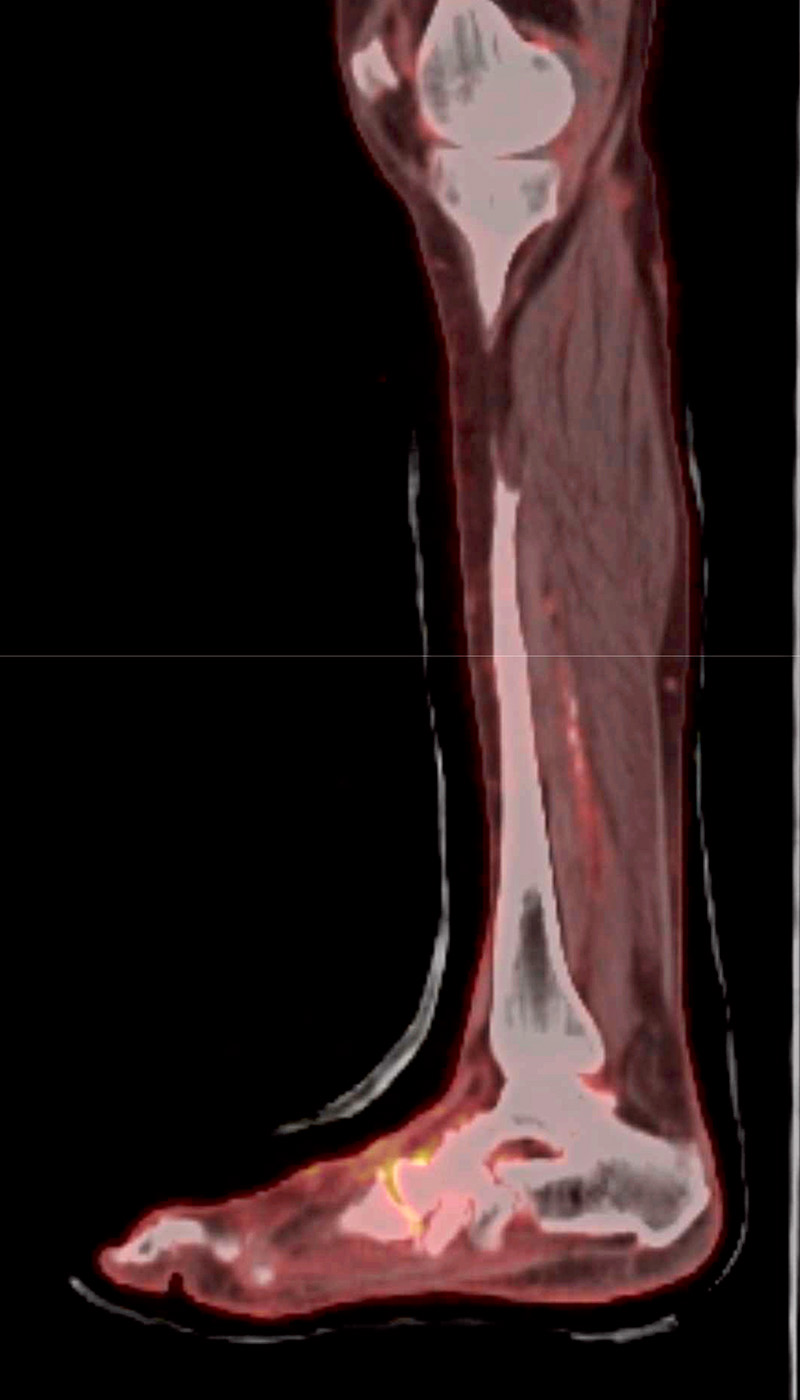

Positronsemissionstomografi med datortomografi (PET-DT) har visats kunna särskilja diagnoserna ännu bättre än MRT [29]. Vid kontraindikation för MRT (till exempel pacemaker) kan skelettskintigrafi användas med hög sensitivitet för Charcotfot, men denna modalitet kan inte alls särskilja Charcotfot från osteomyelit [23].

PET-DT med tecken på aktivitet i Lisfrancs led.